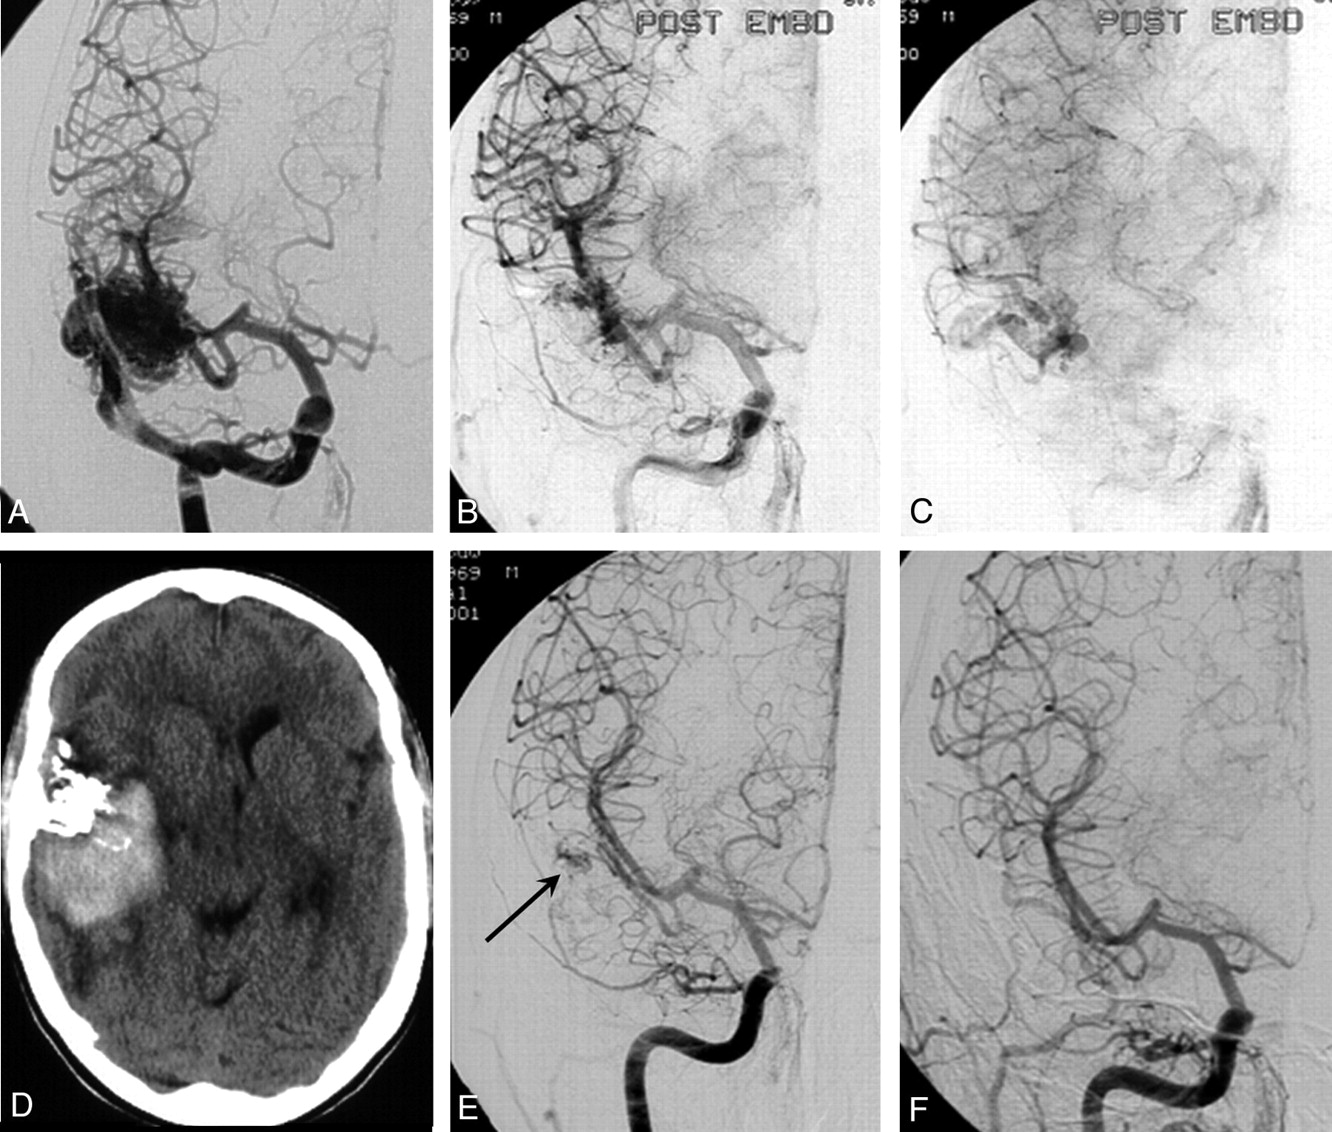

• أول عملية انسداد لأورام الدماغ الوعائية، 1998

تساعد هذه الطريقة في تقليل إمداد الدم لأورام الدماغ وبالتالي تقليصها.